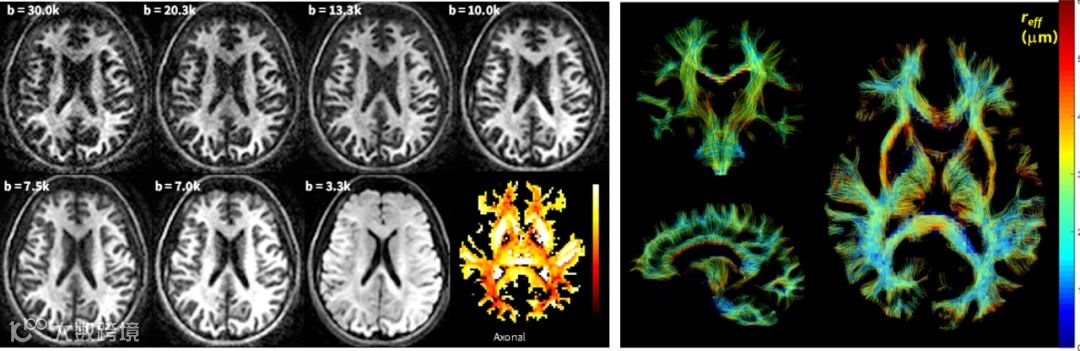

微脑解析:基于SIGNA MAGNUS平台,高梯度场强切换率性能下,使用超高30000B值弥散成像,大幅剔除小轴突测量中不同伪影因素的影响,成功对微脑损伤患者进行了1μm及以下的轴突直径进行解析显示,为微脑的损伤以及机制研究带来全新的临床研究尺度。